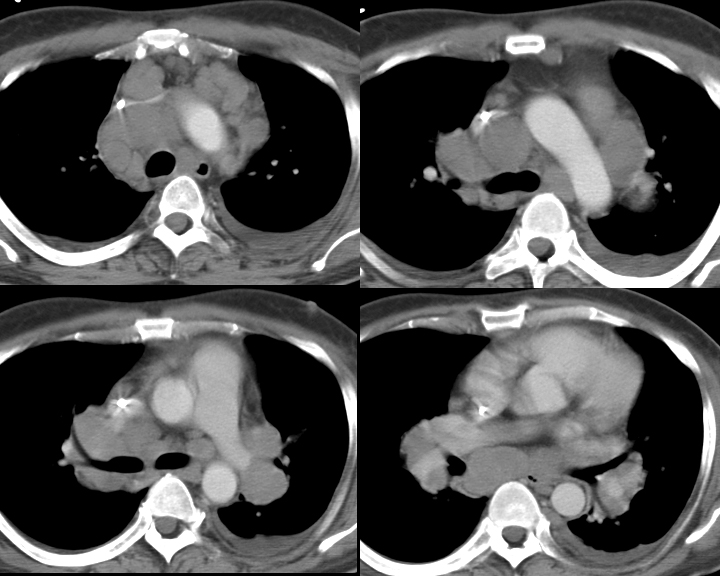

Gallery Mediastinum Lymphoma 2b

2b